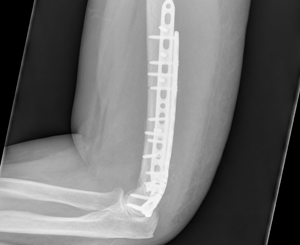

This lady had a displaced fracture at the lower end of the humerus. This was fixed using 2 long pre-contoured Titanium plates allowing for early mobilisation without the need for any splints or casts.